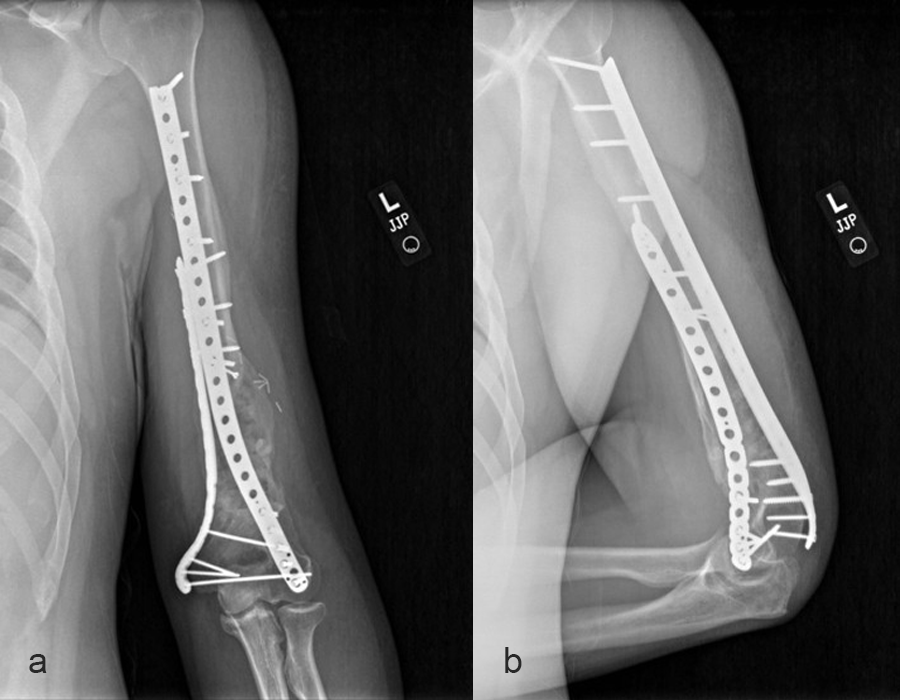

Patient examination revealed a healed incision on the left upper extremity, with varus alignment of the elbow and an elbow range of motion of 90-120°. X-rays revealed a non-union/malunion of the distal humerus and implant failure (Fig 16).

In a first stage, the distal humerus was debrided and devitalized bone was resected, leaving an 8cm defect into which a cement spacer was placed. New plates were inserted to stabilize the fracture (Fig 17 and Fig 18). Cultures taken in the OR were negative.

In October 2022, planning began for the second stage of surgery. A graft cage was planned (Fig 19) to allow the formation of new bone in the 8cm defect.